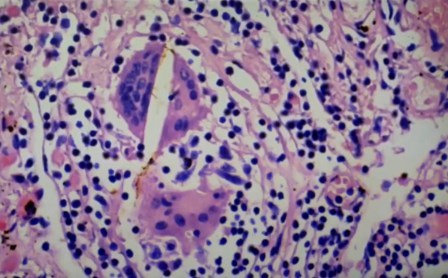

Esta aglomeración está en investigación

Vasos y endotelios, también en investigación, debido a la rareza, que les impide determinar lo que es

Esto no se pudo interpretar, son cosas “rarísimas” en este pulmón, y no solo una, sino varias veces, es decir, en varios fallecidos.

“Esto tampoco se que es, no tengo idea, no es un nervio, creo que es un vaso”, indica.

Eritrocitos grumos

Eritrocitos normales, separados

Otro caso de eritrocitos en grumos en inflamación de vena pulmonar

Caso severo, linfocitos en pared vascular

Infarto pulmonar que no debería ser mortal, se ven los linfocitos